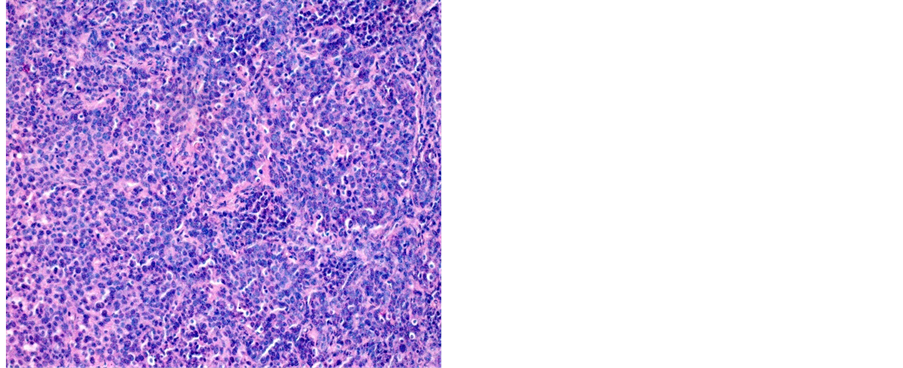

Figure 4. Poorly differentiated SCC (a) 200×; (b) 400×.

Histologically, SCC was the predominant type with 1.687 (81.18%) cases, followed by the ADK with 269 (12.95%) cases. This predominance of the EC was discovered by several African authors. It is notably higher than the value found in the Cameroonian coast (72, 07%) [8] . Other studies have assigned even higher values: Sando et al. −87.6%, Hasiniatsy et al. −88.50%, Nayama et al. −91.6% and Elmajjawi et al. −94% [7] [16] [17] [25] . However, in the West, Mubiayi et al. reported a trend applicable to ours with 81% cases of squamous cell carcinoma. However, more cases of adenocarcinoma were registered in their series, 17% [26] . According to studies, cervical squamous cell carcinoma risk is 74% - 80% higher in women with a first-degree relative with cervical squamous cell carcinoma, compared to the general population [27] . Cervical adenocarcinoma risk is 39% - 69% higher in women with a first-degree relative with cervical squamous cell carcinoma, compared to the general population, a number of studies showed [27] . Cervical squamous cell risk is 15% higher in women who have had 1 full-term pregnancy than in those who have never had; the risk increases with the number of full- term pregnancies [28] . The same study showed that cervical cancer risk among parous women is 77% higher in those under 17 at their first full-term pregnancy than in those aged 25 or more; the risk decreases with age at first full-term pregnancy [28] . There is no association with parity for adenocarcinoma [28] . Cervical squamous cell carcinoma risk is 1.5 times higher in current smokers than in people who have never smoked, and the risk increases with the number of cigarettes smoked per day [14] .